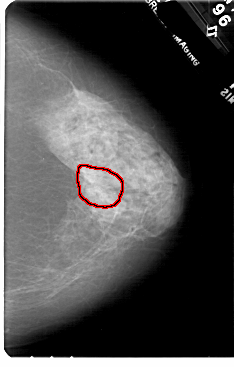

FILE: A_1720_1.RIGHT_CC.OVERLAY

TOTAL_ABNORMALITIES 1

ABNORMALITY 1

LESION_TYPE MASS SHAPE ARCHITECTURAL_DISTORTION MARGINS SPICULATED

ASSESSMENT 4

SUBTLETY 2

PATHOLOGY MALIGNANT

TOTAL_OUTLINES 1

BOUNDARY